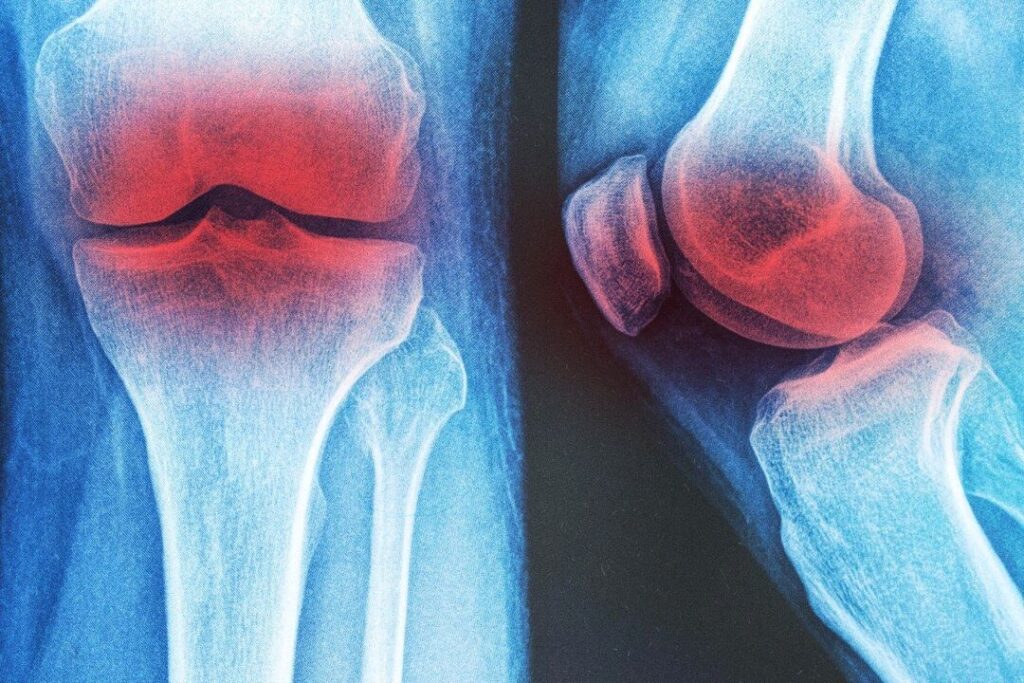

膝の変形性関節症に効く 3つの非薬物療法

膝の変形性関節症の痛みは薬だけに頼らなくても改善可能。研究が示す効果的な3つの非薬物療法とは?